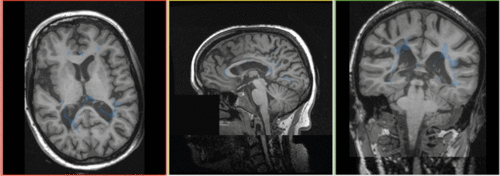

| ||

| fixed image/target | moving image | |

| resampled labelmap in reference space |

| |

| result | resample | segmentation labelmap |

This scenario occurs in many forms whenever we wish to align all the series from a single MRI exam/session into a common space. Alignment is necessary because the subject likely has moved in between series. As additional files we have a labelmap for the moving image we need to move along .

- tag: segmentation labelmap obtained from above FLAIR, to be resampled with result transform